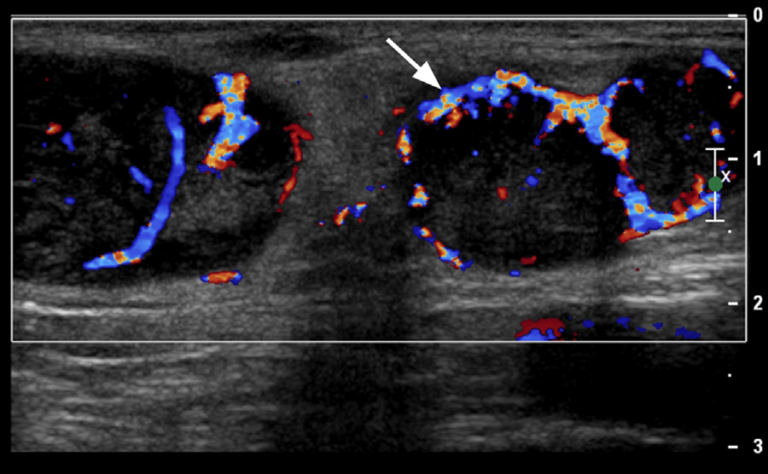

- 造影CTにおいて、リンパ節周囲の脂肪織混濁(perinodal infiltration)が高率に見られる。また、16%程度と必ずしも頻度は高くないが、リンパ節内部の壊死を示唆する内部の増強不良域が見られた場合は、特徴的な所見と考えられる。